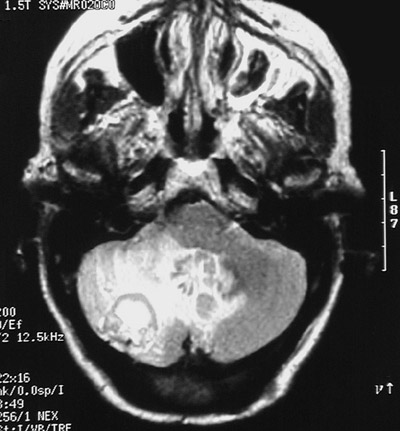

This T2 weighted MRI scan in axial view demonstrates a

cerebellar hemangioblastoma

that is partly cystic. There is also

edema

, which appears bright, adjacent to this well-circumscribed mass in the cerebellum.